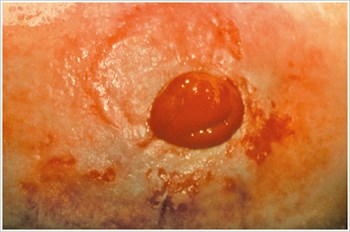

Úlcera por presión

Descripción/causas:

Una úlcera en la zona periestomal debida a una presión excesiva de un cinturón del dispositivo de ostomía, ropa apretada, placa delantera rígida, hernia periestomal o hábitos relacionados con el trabajo.

Síntomas:

- Dolor

- Úlcera de forma irregular

- Fuga de la bolsa

- Menor tiempo de uso